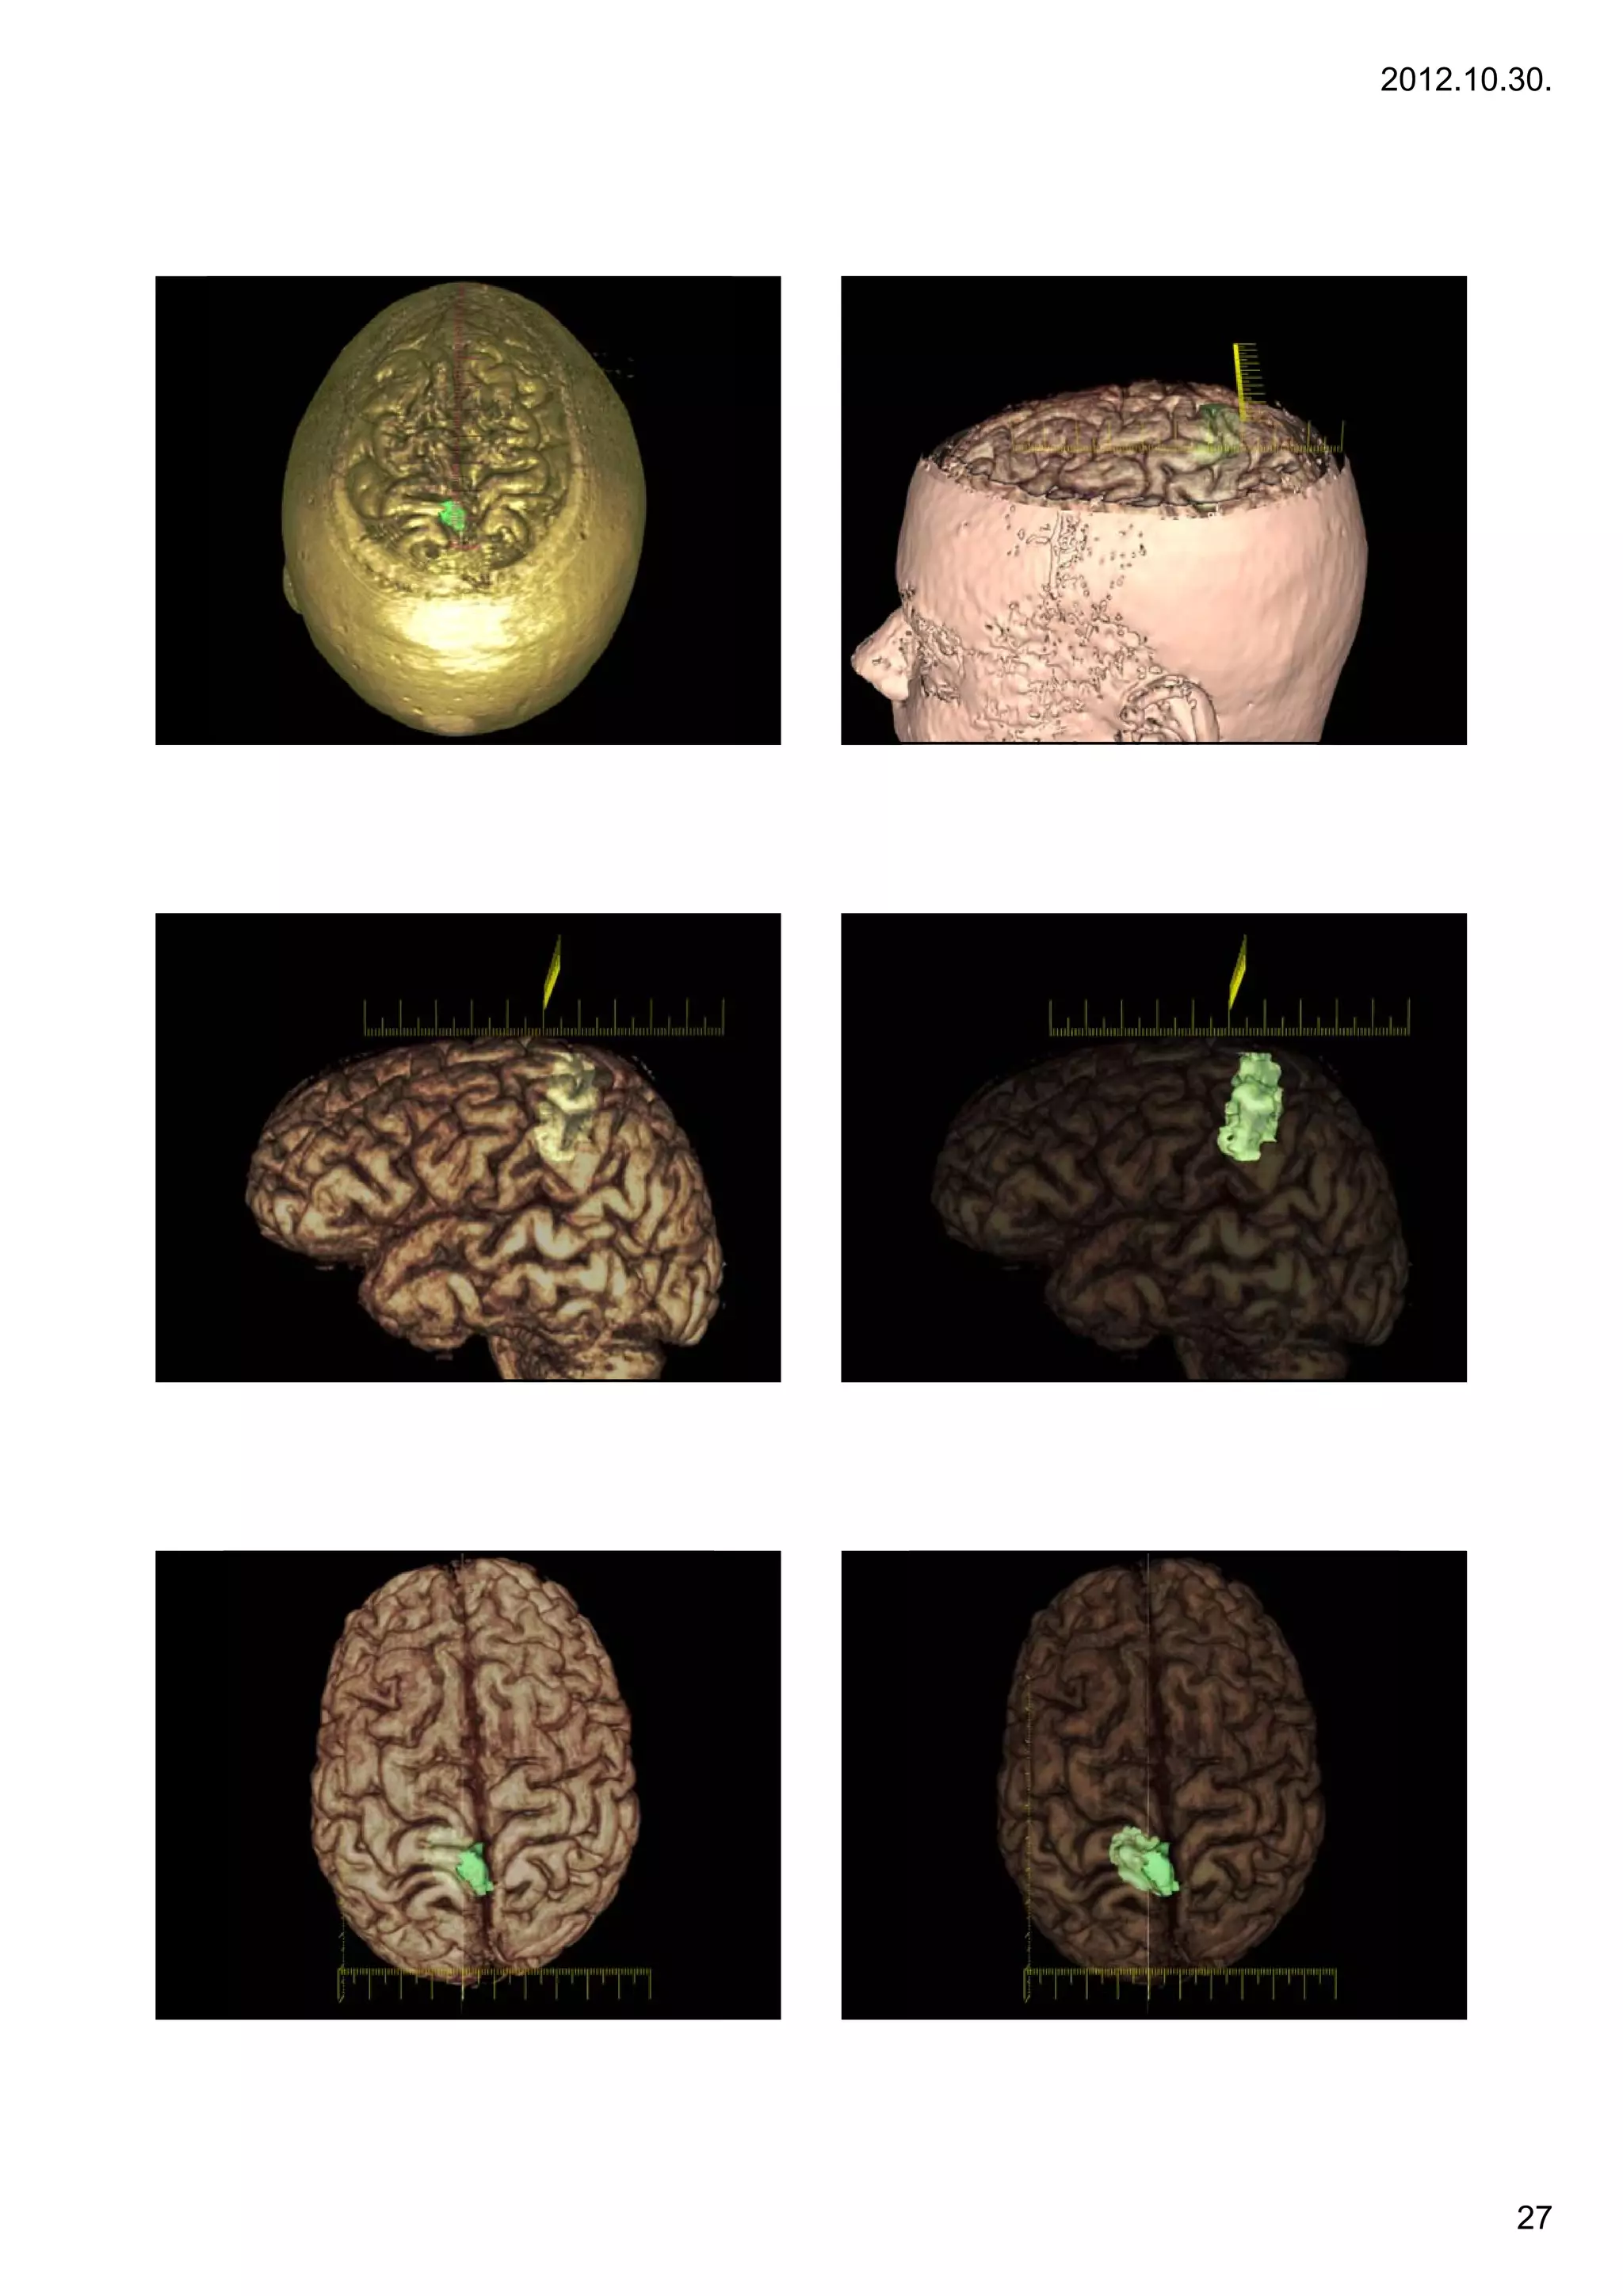

AVMs                                                       Diagnosis by angiography

•Arteriovenous malformation or AVM is an abnormal connection

between veins and arteries, usually congenital. This pathology is widely known because of its

occurrence in the central nervous system, but can appear in any location. An arteriovenous

malformation is a vascular anomaly. It is a RASopathy. The Spetzler-Martin grading system

developed at the Barrow Neurological Institute is utilized by neurosurgeons to determine

operative versus nonoperative management when approaching these lesions.

Diagnosis by angiography                                                            Diagnosis by MRI (T1 and T2-w)

26

27